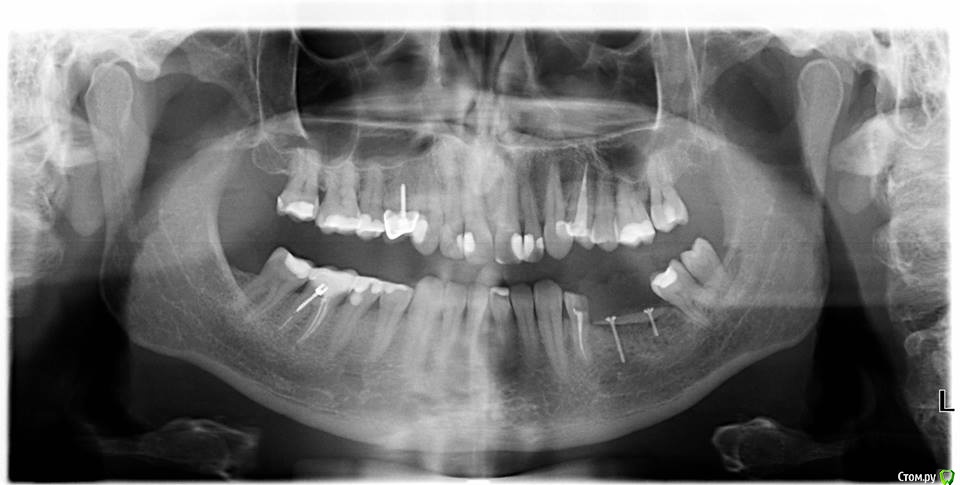

Nazim_NV86 Опубликовано 3 апреля, 2017 Поделиться Опубликовано 3 апреля, 2017 Доброе время суток коллеги. Вот такой вот вертикальный дефект. Была неудачная попытка костной пластики. Собираюсь делать ламинами, но хотел бы почитать ваши рекомендации, а возможно и ссылки на похожие операции. Ссылка на комментарий

kamranchick Опубликовано 4 апреля, 2017 Поделиться Опубликовано 4 апреля, 2017 Доброе время суток коллеги. Вот такой вот вертикальный дефект. Была неудачная попытка костной пластики. Собираюсь делать ламинами, но хотел бы почитать ваши рекомендации, а возможно и ссылки на похожие операции. Ссылка на комментарий